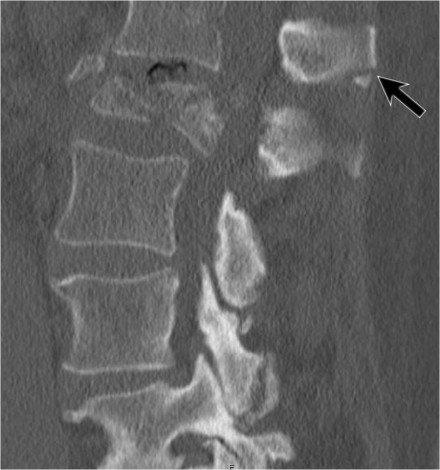

The images are of a patient with a typical bamboo spine as a result of ankylosing spondylitis.

After a fall on his back no fracture was seen on the x-rays.

However the CT shows a thin fracture line through the anterior side of the vertebral body and also through the spinous process.

Continue with the MR-images.

Look at the images.

What are the findings?

Then scroll to the next images.

The findings are:

- Vertebral bodies show marrow edema as a result of a fracture.

- Torn flaval ligament (yellow arrow).

- Fractures through the posterior elements (red arrows).

The TLICS-score is high, because there is distraction and injury to the PLC.